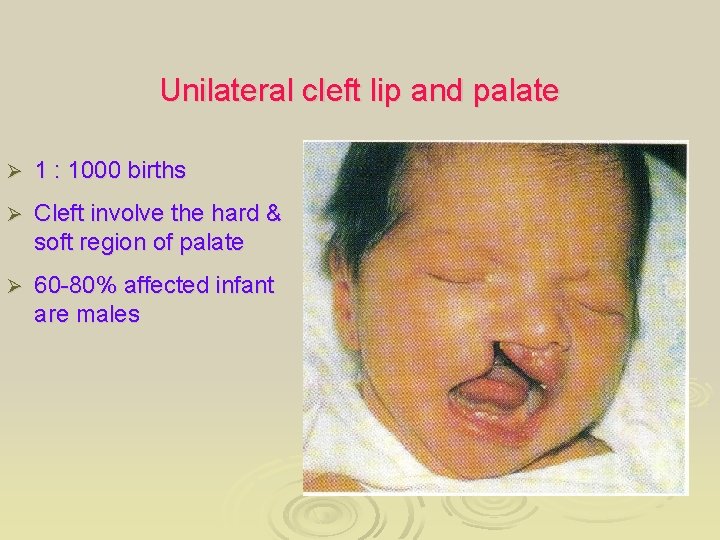

Unilateral cleft lip and palate Ø 1 : 1000 births Ø Cleft involve the hard & soft region of palate Ø 60 -80% affected infant are males